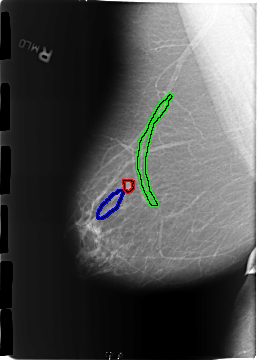

B_3172_1.RIGHT_MLO

FILE: B_3172_1.RIGHT_MLO.OVERLAY

TOTAL_ABNORMALITIES 3

ABNORMALITY 1

LESION_TYPE MASS SHAPE LOBULATED-LYMPH_NODE MARGINS CIRCUMSCRIBED

ASSESSMENT 2

SUBTLETY 4

PATHOLOGY BENIGN_WITHOUT_CALLBACK

TOTAL_OUTLINES 1

BOUNDARY

ABNORMALITY 2

ABNORMALITY 3